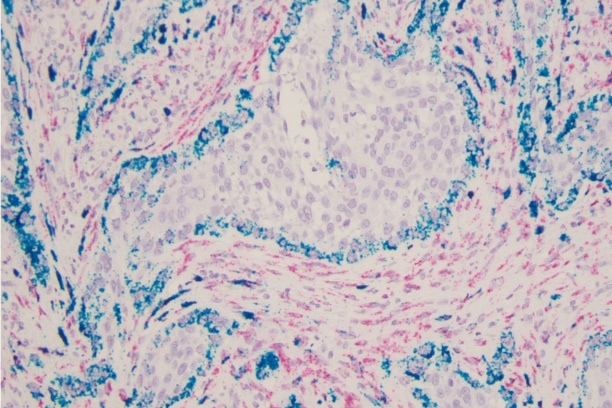

The Weiss laboratory is focused on understanding the molecular and immunologic mechanisms of thyroid cancer invasion and metastasis. While most thyroid cancer patients respond well to standard therapy, there are few options for those with widely metastatic or recurrent disease. Predicting which patients will have aggressive disease and treating those patients is an important goal in the field. The goal of the laboratory is to understand the signaling mechanisms and immune microenvironment responsible for the aggressive malignant behaviors of metastatic and recurrent disease. Projects include defining the role of Wnt signaling within the current molecular landscape of papillary thyroid carcinoma. The laboratory also uses computational immunogenomics to define the immunologic microenvironment within aggressive thyroid cancer subtypes to improve treatment and malignancy risk prediction at the time of biopsy.